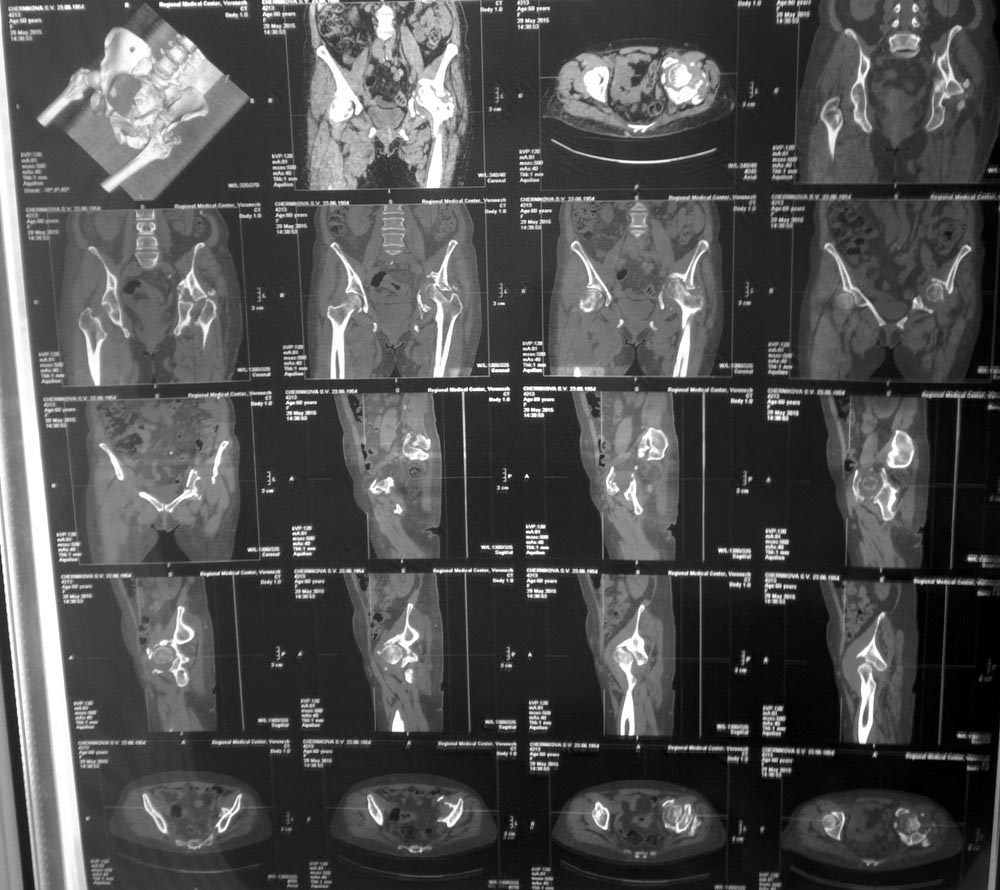

Женщина, 62 г, ДТП 25.11.2014. Перелом ВВ, лонной и седалищной костей с

нарушением непрерывности тазового кольца, частичный разрыв КПС, гнойная

рана бедра, все слева.

Лечилась консервативно, вытяжение не удалось, полное заживление раны

через 5 мес.

Левая конечность неопороспособна, но явных признаков некроза головки

нет. Пытаться выполнить остеосинтез при сроках 8 месяцев абсолютно

нецелесообразно? Если неизбежно эндопротезировать, то поделитесь

мнениями о предпочтительной тактике: как лучше поступить с передней

колонной, сделать пластику ВВ аутокостью, необходимо ли кольцо

Бурш-Шнайдера/Октопус?